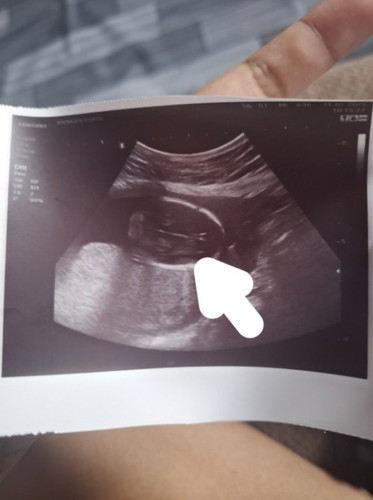

แม่ๆบ้านไหนดูออกบ้างค่ะว่าส่วนไหนของร่างกายแม่ไม่มั่นใจว่าใช่หน้าหรือป่าว

19สัปดาห์4วัน

น่าจะช่วงหัวน้อง ในสมองน้องหรือเปล่าคะ คุณหมอไม่แจ้งหรอคะแม่